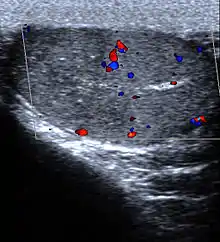

Imagerie

L'échographie est utile si la cause n'est pas retrouvée grâce aux examen ci-dessus[7]. Si le diagnostic de torsion est certain, l'échographie ne doit pas retarder la prise en charge chirurgicale[5].